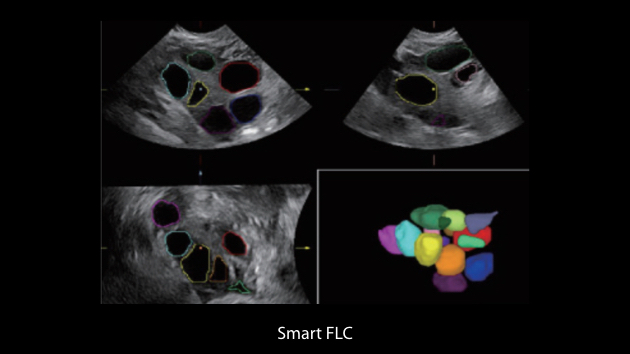

Obrazy kliniczne